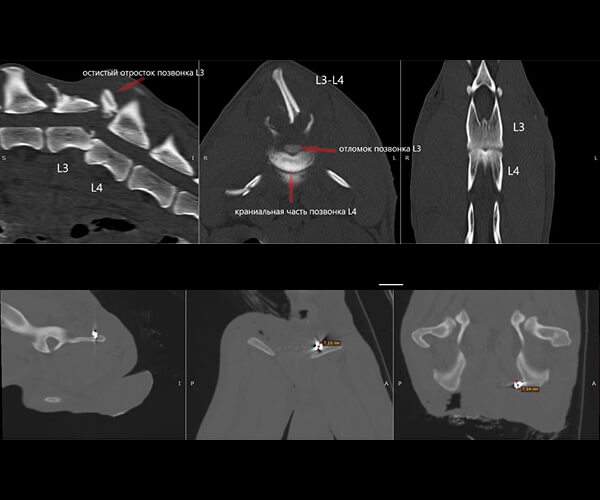

Сейчас в теле щенка застряли пули, повреждён позвоночник и спинной мозг. Он не может лечь, ест и спит только сидя, и каждую минуту терпит боль.

Врачи говорят, что полностью восстановить чувствительность уже не получится. Но у Зухрая есть шанс облегчить страдания и прожить жизнь без постоянной боли. Для этого нужны обследования и лечение в Москве.